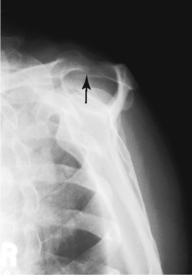

Scapular Y lateral—anterior oblique position and Neer method (S)

Scapular Y lateral and Neer method critique